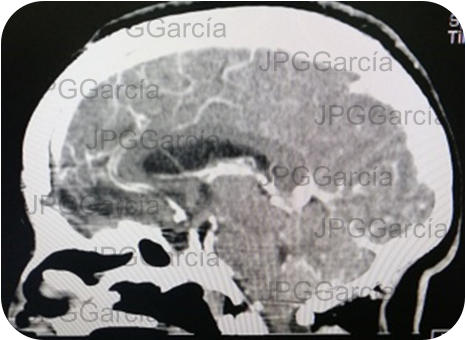

Meningioma del plano esfenoidal Imagen de resonancia magnética corte sagital